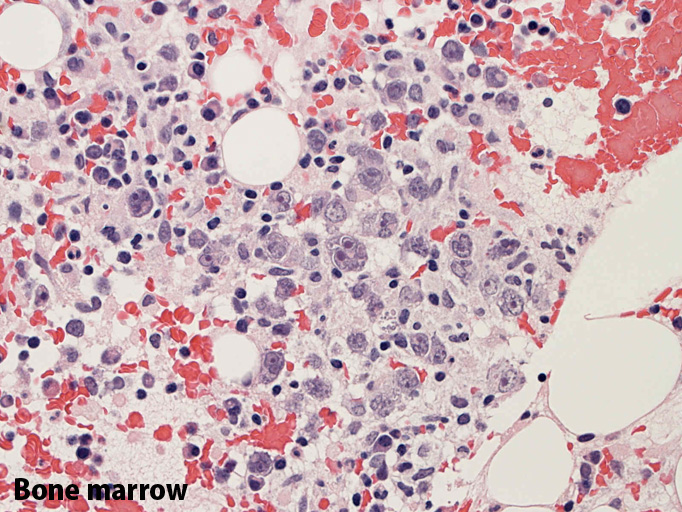

骨髄;細動脈内のみに腫瘍細胞が認められた。類洞や髄内での増殖は見られなかった。

骨髄穿刺吸引では発見できなかった原因のようです。骨髄生検で細動脈がとれないと診断に結びつかなかったでしょう。)

骨髄の組織所見